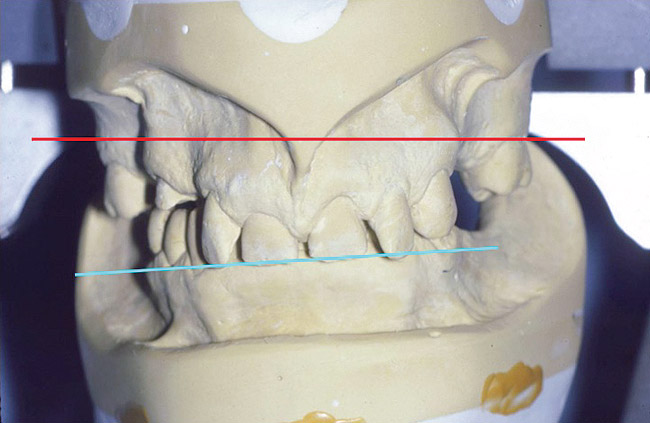

Figure 10. The lower cast is mounted in centric relation, allowing the infero-superior axis of 3D VDO to be increased or decreased.

Figure 10

Figure 12. Mounted casts. Maxillary anterior plane occlusion appears not parallel to the posterior bar of the articulator, which is parallel to the floor and perpendicular to the jaw closure path. When the maxillary removable partial denture prosthesis is made, the posterior plane will be parallel to the posterior articulator bar and thus perpendicular to the path of closure. The incisional closure contact was appropriate on both central incisors; however, as the laterals did not contact. No change in the esthetics of the anterior plane was made per patient preference.

Figure 12